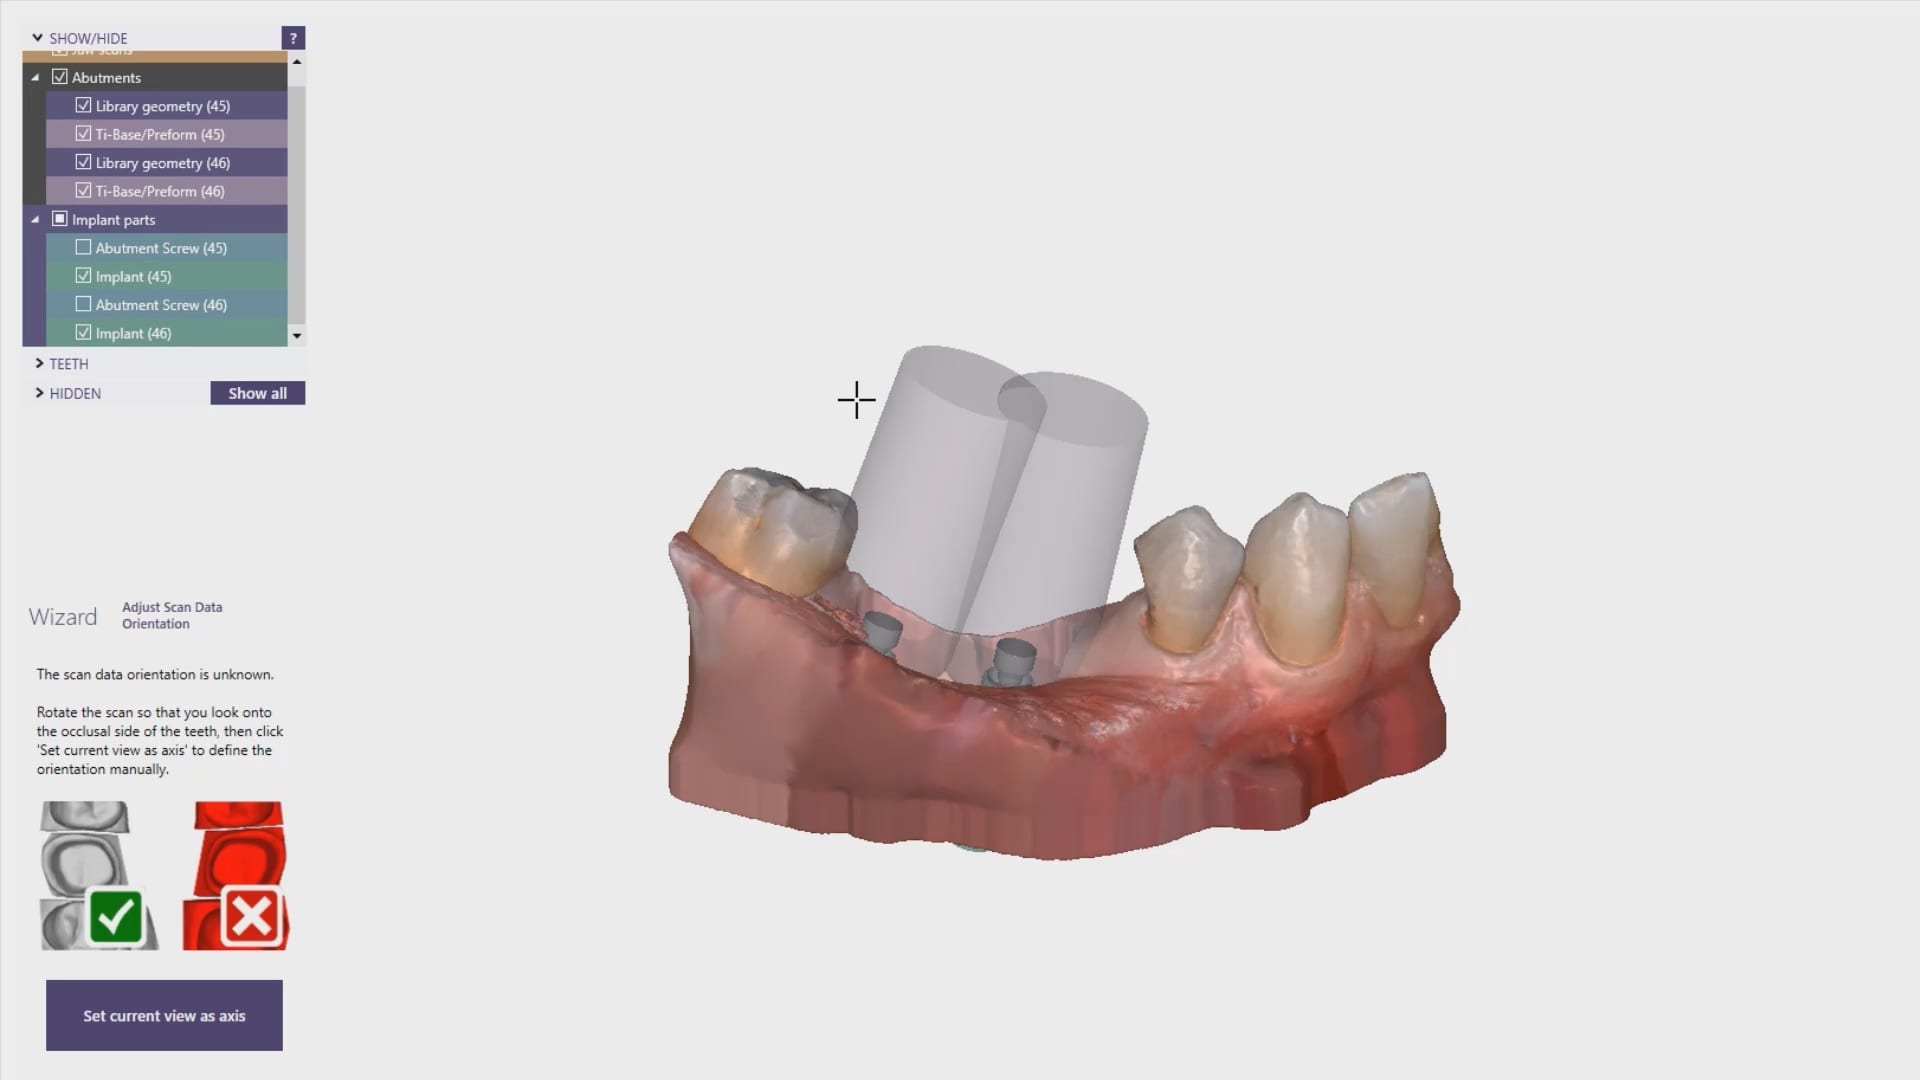

Automatic Scanbody Detection and Auto-Import Into Exocad and Immediate Fixture Identification

August 22, 2019A new feature coming to Medit i500 is the automatic detection of scanbodies while you are imaging. In this clinical case, two implants are placed in the lower left quadrant […]